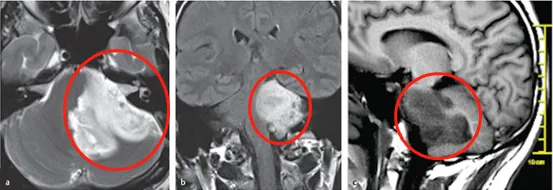

经磁共振成像(MRI)检查发现脑干区域存在巨大肿瘤,累及左侧桥脑、脑桥臂及小脑,肿瘤压迫邻近面神经与听神经导致上述症状。图a、b、c显示脑干巨大占位病变,图d术前扩散张量成像可见肿瘤压迫致皮质脊髓束移位。

鉴于不能排除低级别胶质瘤可能,且存在明显占位效应,医疗团队建议尽早手术明确病理诊断。但由于脑干手术复杂度高,瘫痪风险显著。治疗团队INC德国巴特朗菲教授采用乙状窦后入路,经左侧桥小脑角暴露肿瘤,成功切除50%以上瘤体。因肿瘤累及多数颅神经(CNs V-XI),为避免严重神经功能损伤未行全切。术后除短暂性步态共济失调外,未出现新发神经功能障碍。

术后病理确诊为胶质母细胞瘤,IDH1与BRAF呈阴性,p53蛋白局部阳性率达50%,O6-甲基鸟嘌呤DNA甲基转移酶(MGMT)启动子高度甲基化。患者按Stupp方案完成放化疗,随访MRI显示残余肿瘤逐渐消退。术后4年随访显示患者可完全独立生活,延髓(图e)与脑桥(图f)轴位T1加权增强MRI未见肿瘤复发征象。